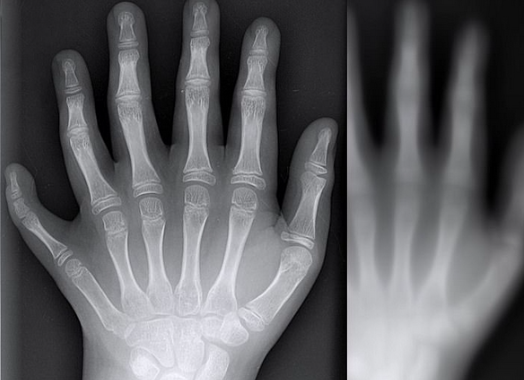

辛追夫人:千年不腐的女尸

【大家好,我是铃木,第一次写灵异科普,写得不好,多请指教。 还有,我马上就要被那个恐怖的学校逮回去了,只能中秋节再回来…… 以第一视角展开叙述,差不多是我的一篇游记。篇幅有限,只针对女尸,不讲陪葬物。有复制粘贴,侵删】 一 1972年,湖南省马王堆出土一惊世墓葬。集举国之力,技术却仍没跟上,导致墓中一湿尸轻微腐化。 经检验,此尸距今已有两千余年历史,出土时却完好无损,皮肤尚有光泽弹性,宛若刚刚下葬…- 18.9k